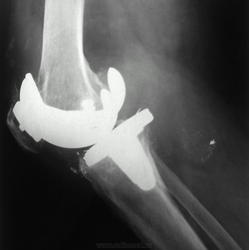

Снимки 4,5,6 пациентки, которой была сделана резекция бедренной кости с эндопротезированием коленного сустава 30 лет назад по поводу остеосаркомы. Расшатывание эндопротеза клинически стало себя проявлять 5 лет назад (снимок 4), далее довольно быстро прогрессировало, что по-видимому усугубилось присоединившимся остеомиелитом (снимки 5, 6 - теперешние). Пришлось выполнить ампутацию, тем не менее, человеку дали 25 лет нормальной, полноценной жизни.